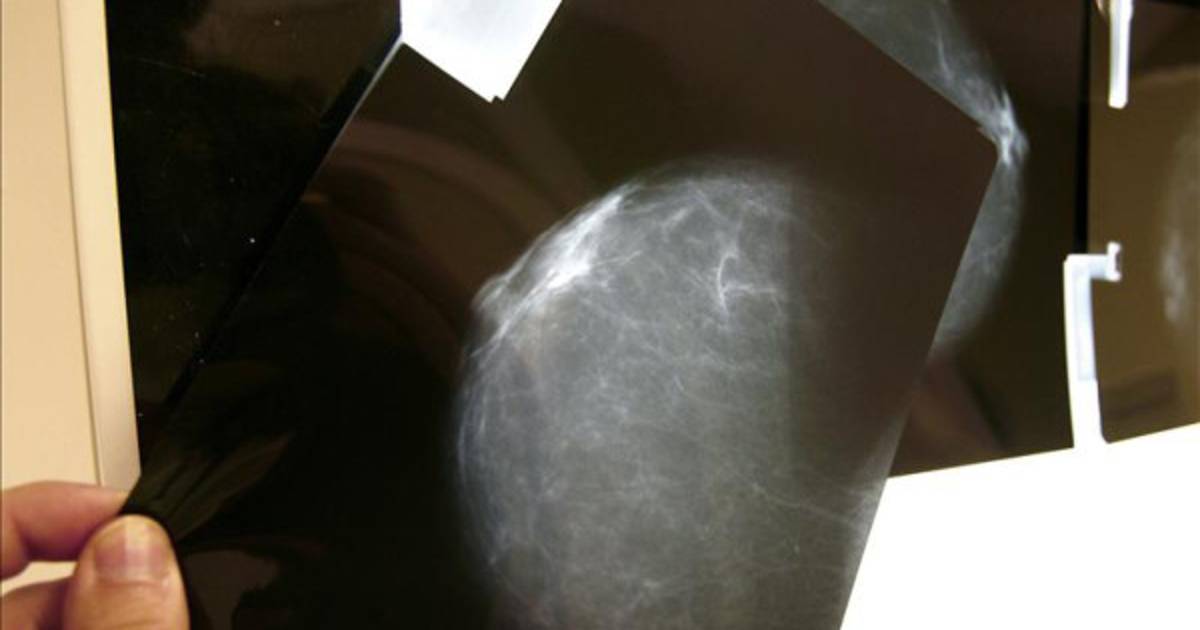

A nivel global, en 2012, el cáncer más diagnosticado fue el de pulmón, con 1,8 millones de nuevos casos, seguido del de pecho, con 1,7 millones, y el de colon, con 1,4 millones.